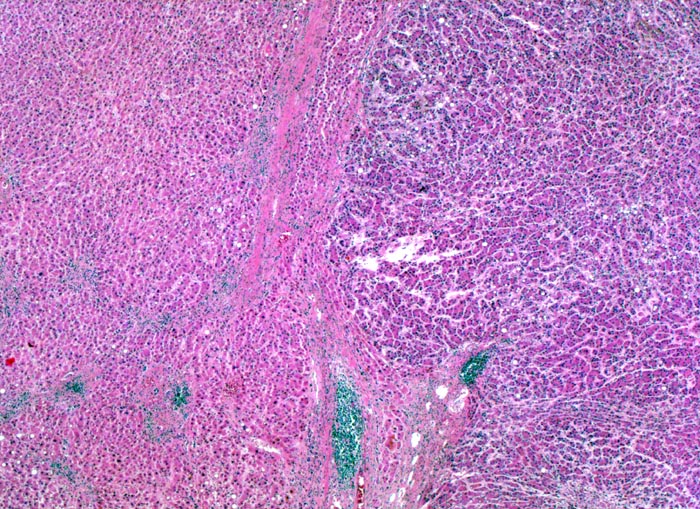

Makroskopisch imponiert das hepatozelluläre Karzinom als solitäre grosse Tumormasse, als zahlreiche zirrhoseartige Knoten oder als scharf begrenzter Knoten mit oder ohne Kapsel. Die tumorfreie Leber ist in der Mehrheit der Fälle zirrhotisch umgebaut. Mikroskopisch bilden die Tumorzellen mehr als 2 Zellen breite Trabekel (> 1237), kompakte Tumormassen (> 1229) oder pseudoglanduläre Strukturen (dilatierte Canaliculi) (> 1212) (> 1199). Desmoplastisches Bindegewebe fehlt meist. Innerhalb des Tumors fehlen Portalfelder. Es finden sich lediglich Arterien. Etwa bei der Hälfte der Karzinome lässt sich intrazytoplasmatische oder intracanaliculäre Galle (> 1238) nachweisen. Immunhistochemisch lassen sich mit einem polyklonalen Antikörper gegen Carcinoembryonales Antigen (CEA) Gallecanaliculi zwischen den Tumorzellen nachweisen. Die Tumorzellen bilden keinen Schleim.

• Scharf begrenzter bekapselter Tumor.

• Innerhalb des Tumors Blutgefässe, aber keine Portalfelder.

• Die Tumorzellen bilden Trabekel, welche überwiegend mehr als 2 Zellen breit sind und Pseudodrüsen.

• Sinusoidartige Blutgefässe mit Endothelauskleidung verlaufen zwischen den Trabekeln und den Pseudodrüsen.

• Die Tumorzellen erinnern an normale Hepatozyten, sind aber kleiner als die Hepatozyten und die Kern-Zytoplasmarelation ist deutlich erhöht. Das Zytoplasma ist basophiler als das der angrenzenden Hepatozyten.

• Tumorfreies Parenchym mit chronischer viraler Hepatitis (B und D): dichtes chronisches Entzündungsinfiltrat in den Portalfeldern übergreifend auf das Parenchym (Interfacehepatitis). Spärliche intralobuläre Entzündung mit Einzelzellnekrosen (Apoptosen). Fibrose der Portalfelder mit Septenbildung und unvollständigem zirrhotischem Umbau.